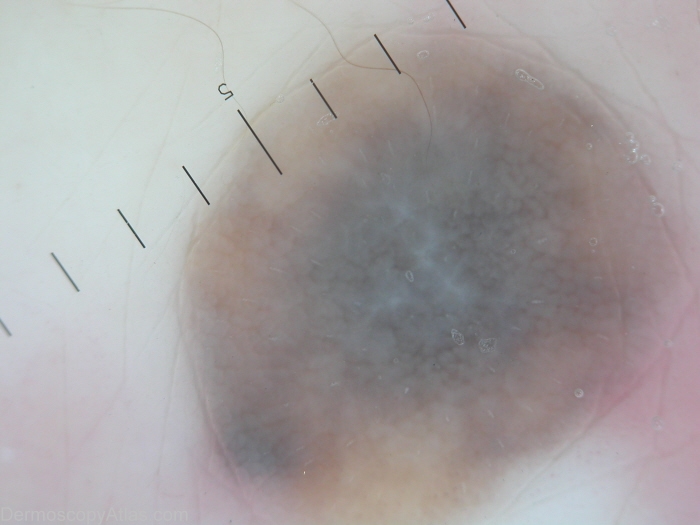

Diagnosis - Fibrosing type of blue nevus

Diagnosis: Fibrosing type of blue nevus